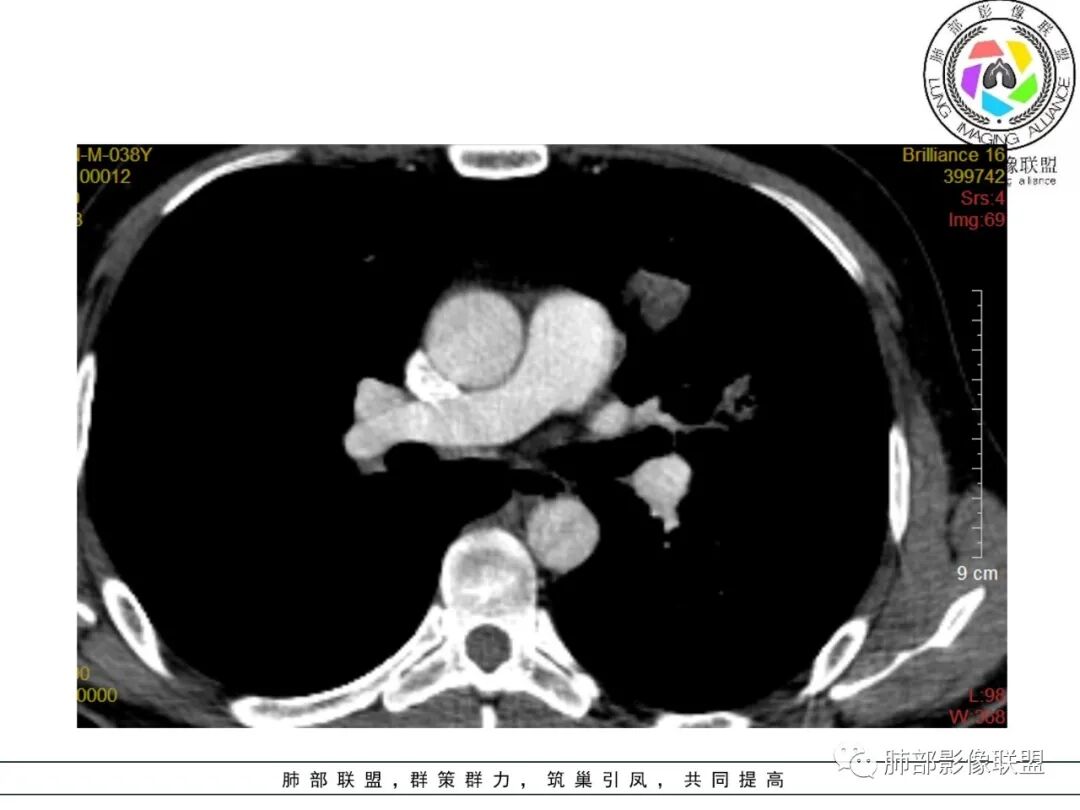

尘缘:中年男性,咳嗽咳痰伴乏力多汗,无发热,偶有畏寒。期间至某中医院治疗服中药后,症状好转。白细胞与血沉稍高。影像表现:左上肺团块状影(增强后CT值约22,伴有血管漂浮),中间支气管明显扩张,伴有小空洞形成,周围有晕,右下肺多发团块状影(增强后CT值约48),无明显支扩,伴胸膜下多发小结节,13天后复查,左上肺主病灶无明显变化,其他病灶范围有缩小,空洞消失,右下肺病灶变化不明显。

可能诊断:1、二元:左上肺淋巴瘤,强化程度较轻,明显支扩,血管漂浮,治疗后左上肺病灶有好转(考虑为周围渗出减轻,空洞消失所致),右下肺感染性病变,有感染的临床症状及白细胞增高,伴周围多发结节(卫星灶),治疗后无明显变化。病原体:隐球可能性大,鉴别结核,非典。2、一元:整体都考虑感染,那就形成了多形,多态,结核要考虑在前面,临床有咳嗽,咳痰,伴乏力,多汗,支持,影像也可以。一元隐球,左肺病灶形态不支持,支扩太明显,强化程度两肺相差大,所以可能较小。一元类鼻疽,没有糖尿病史,没有下田劳作史,可能小,再加上临床症状无发热,影像无明显SPE改变,无其他系统多发脓肿,而且中药治疗还有一定效果,不太符合。

2、影像资料:双肺多发的小结节、斑片状及不规则型的实性病灶,周围有晕,沿支气管血管束分布,部分的病灶周围可见磨玻璃样影、支气管的扩张以及小的空洞。增强扫描病灶,轻度强化内部见支气管造影征。部分的病灶,支气管有扩张,内壁凹凸不平的改变,纵隔淋巴结未见肿大。病灶整体的形态还是多样化,部分位于胸膜下。

3、治疗:经氟康唑治疗2周后,影像上以边缘的磨玻璃样病灶的吸收为主。